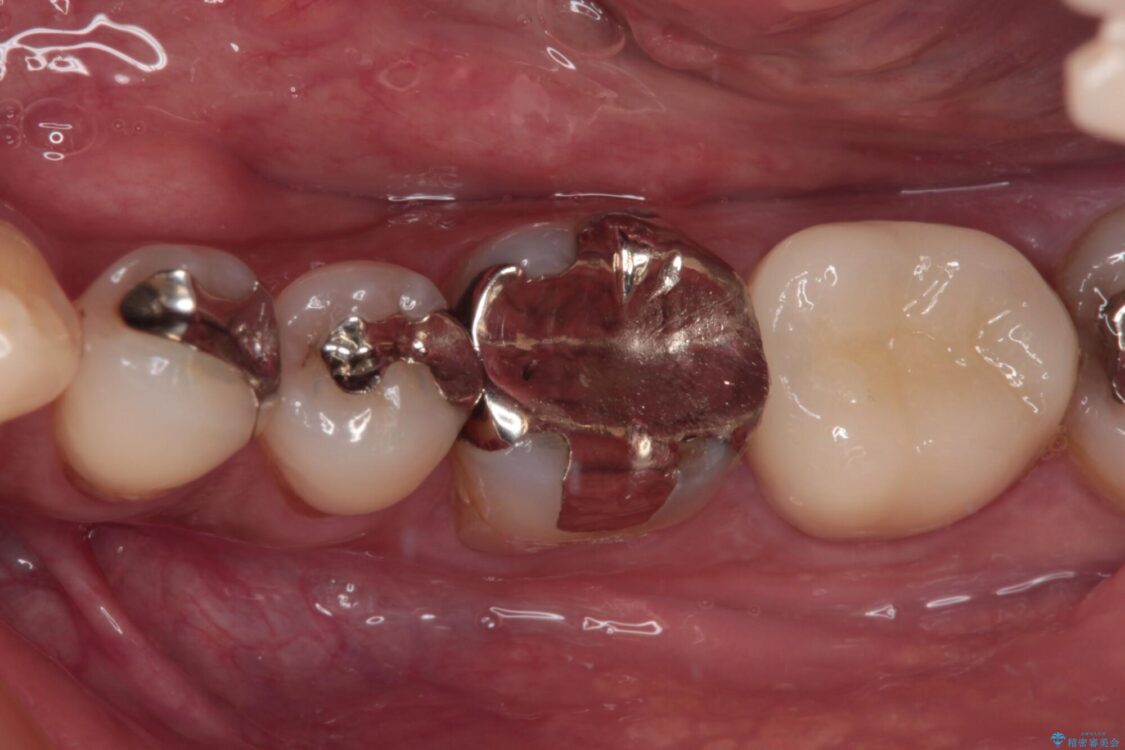

神経組織を部分的に除去することが分かっていたため、ラバーダムなどの環境を整え、無菌的環境下にて処置を進めて行きました。

虫歯は深くまで進行しており、歯冠部の神経から出血が認められました。神経を部分的に除去したところ出血が治まったので、生体親和性の非常に高いセメントにて充填し、仮封をしました。

後日状態を確認したところ、残された神経に異常は認められませんでした。

治療途中

• 治療をしても違和感の続く奥歯 神経を極力残した虫歯治療 治療途中画像